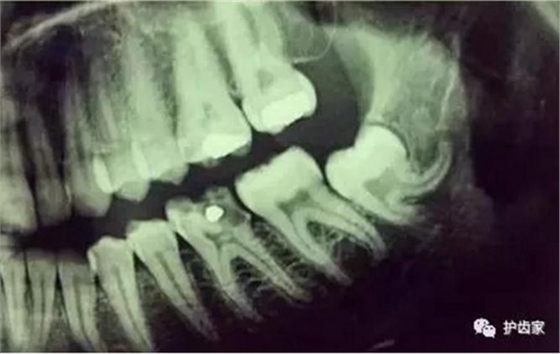

拍片是為了了解智齒周圍情況,也是為了了解智齒結構,牙根結構千變萬化,有可能是融合成一個根,也可能是八爪根。不同牙根不同位置及方向,只有通過拍片來確認。

通過拍片可以了解牙齒本身:生長方向,牙根數目,牙根是否彎曲,膨大等。

與重要解剖結構的位置關系:如上頜磨牙與上頜竇的關系;下頜磨牙與下頜神經管的關系;兒童在混合牙列期恒牙與乳牙胚的關系等??梢詼p少拔牙的風險。

預知其他病變:如頜骨內有無埋伏牙,多生牙,囊腫等。